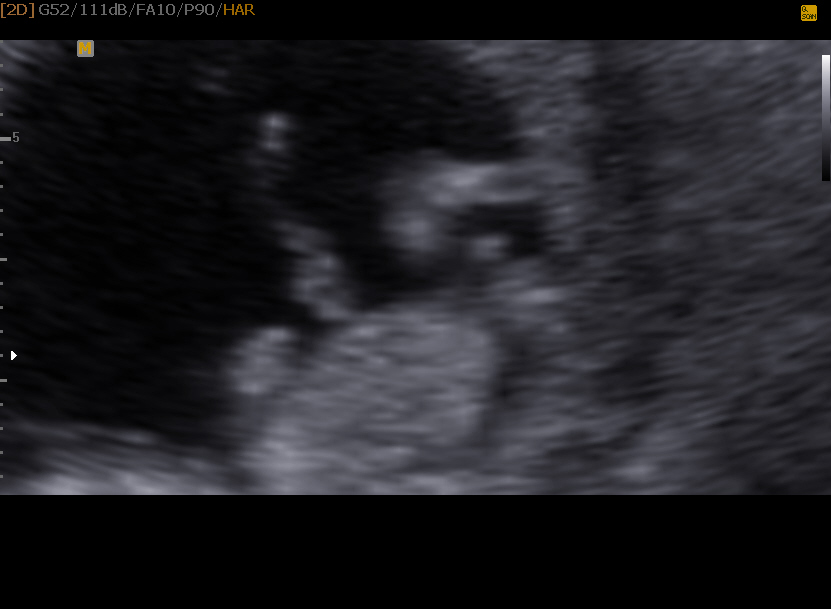

Attachment 17725Attachment 17726

I vote boy too

Kinda hard to tell, but I'm a boy vote too.